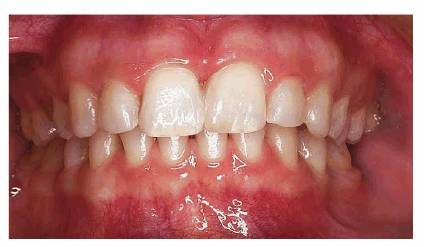

RESULT: Approximately 4 months of treatment were necessary to completely

close and transform the patient's unattractive smile into an attractive one

(see Figures 23-2K

and L). The

appliance was designed to be as unobtrusive as possible. Because of the

patient's motivation and ability to tolerate the appliance, the movement was

accomplished in less time than expected. Twenty-five years later, the patient

wanted to update her smile. Following bleaching treatments, two porcelain

laminates were fabricated for the central incisors (Figure 23-2M

Figure 23-2K and L: A combination of minor orthodontic and restorative treatment helped to improve the smile in only 4 months.

Figure 23-2M: Twenty-five years later, the patient wanted to update her smile. Bleaching treatments and two porcelain laminates were fabricated for the two central incisors to update the patient's smile to her satisfaction.